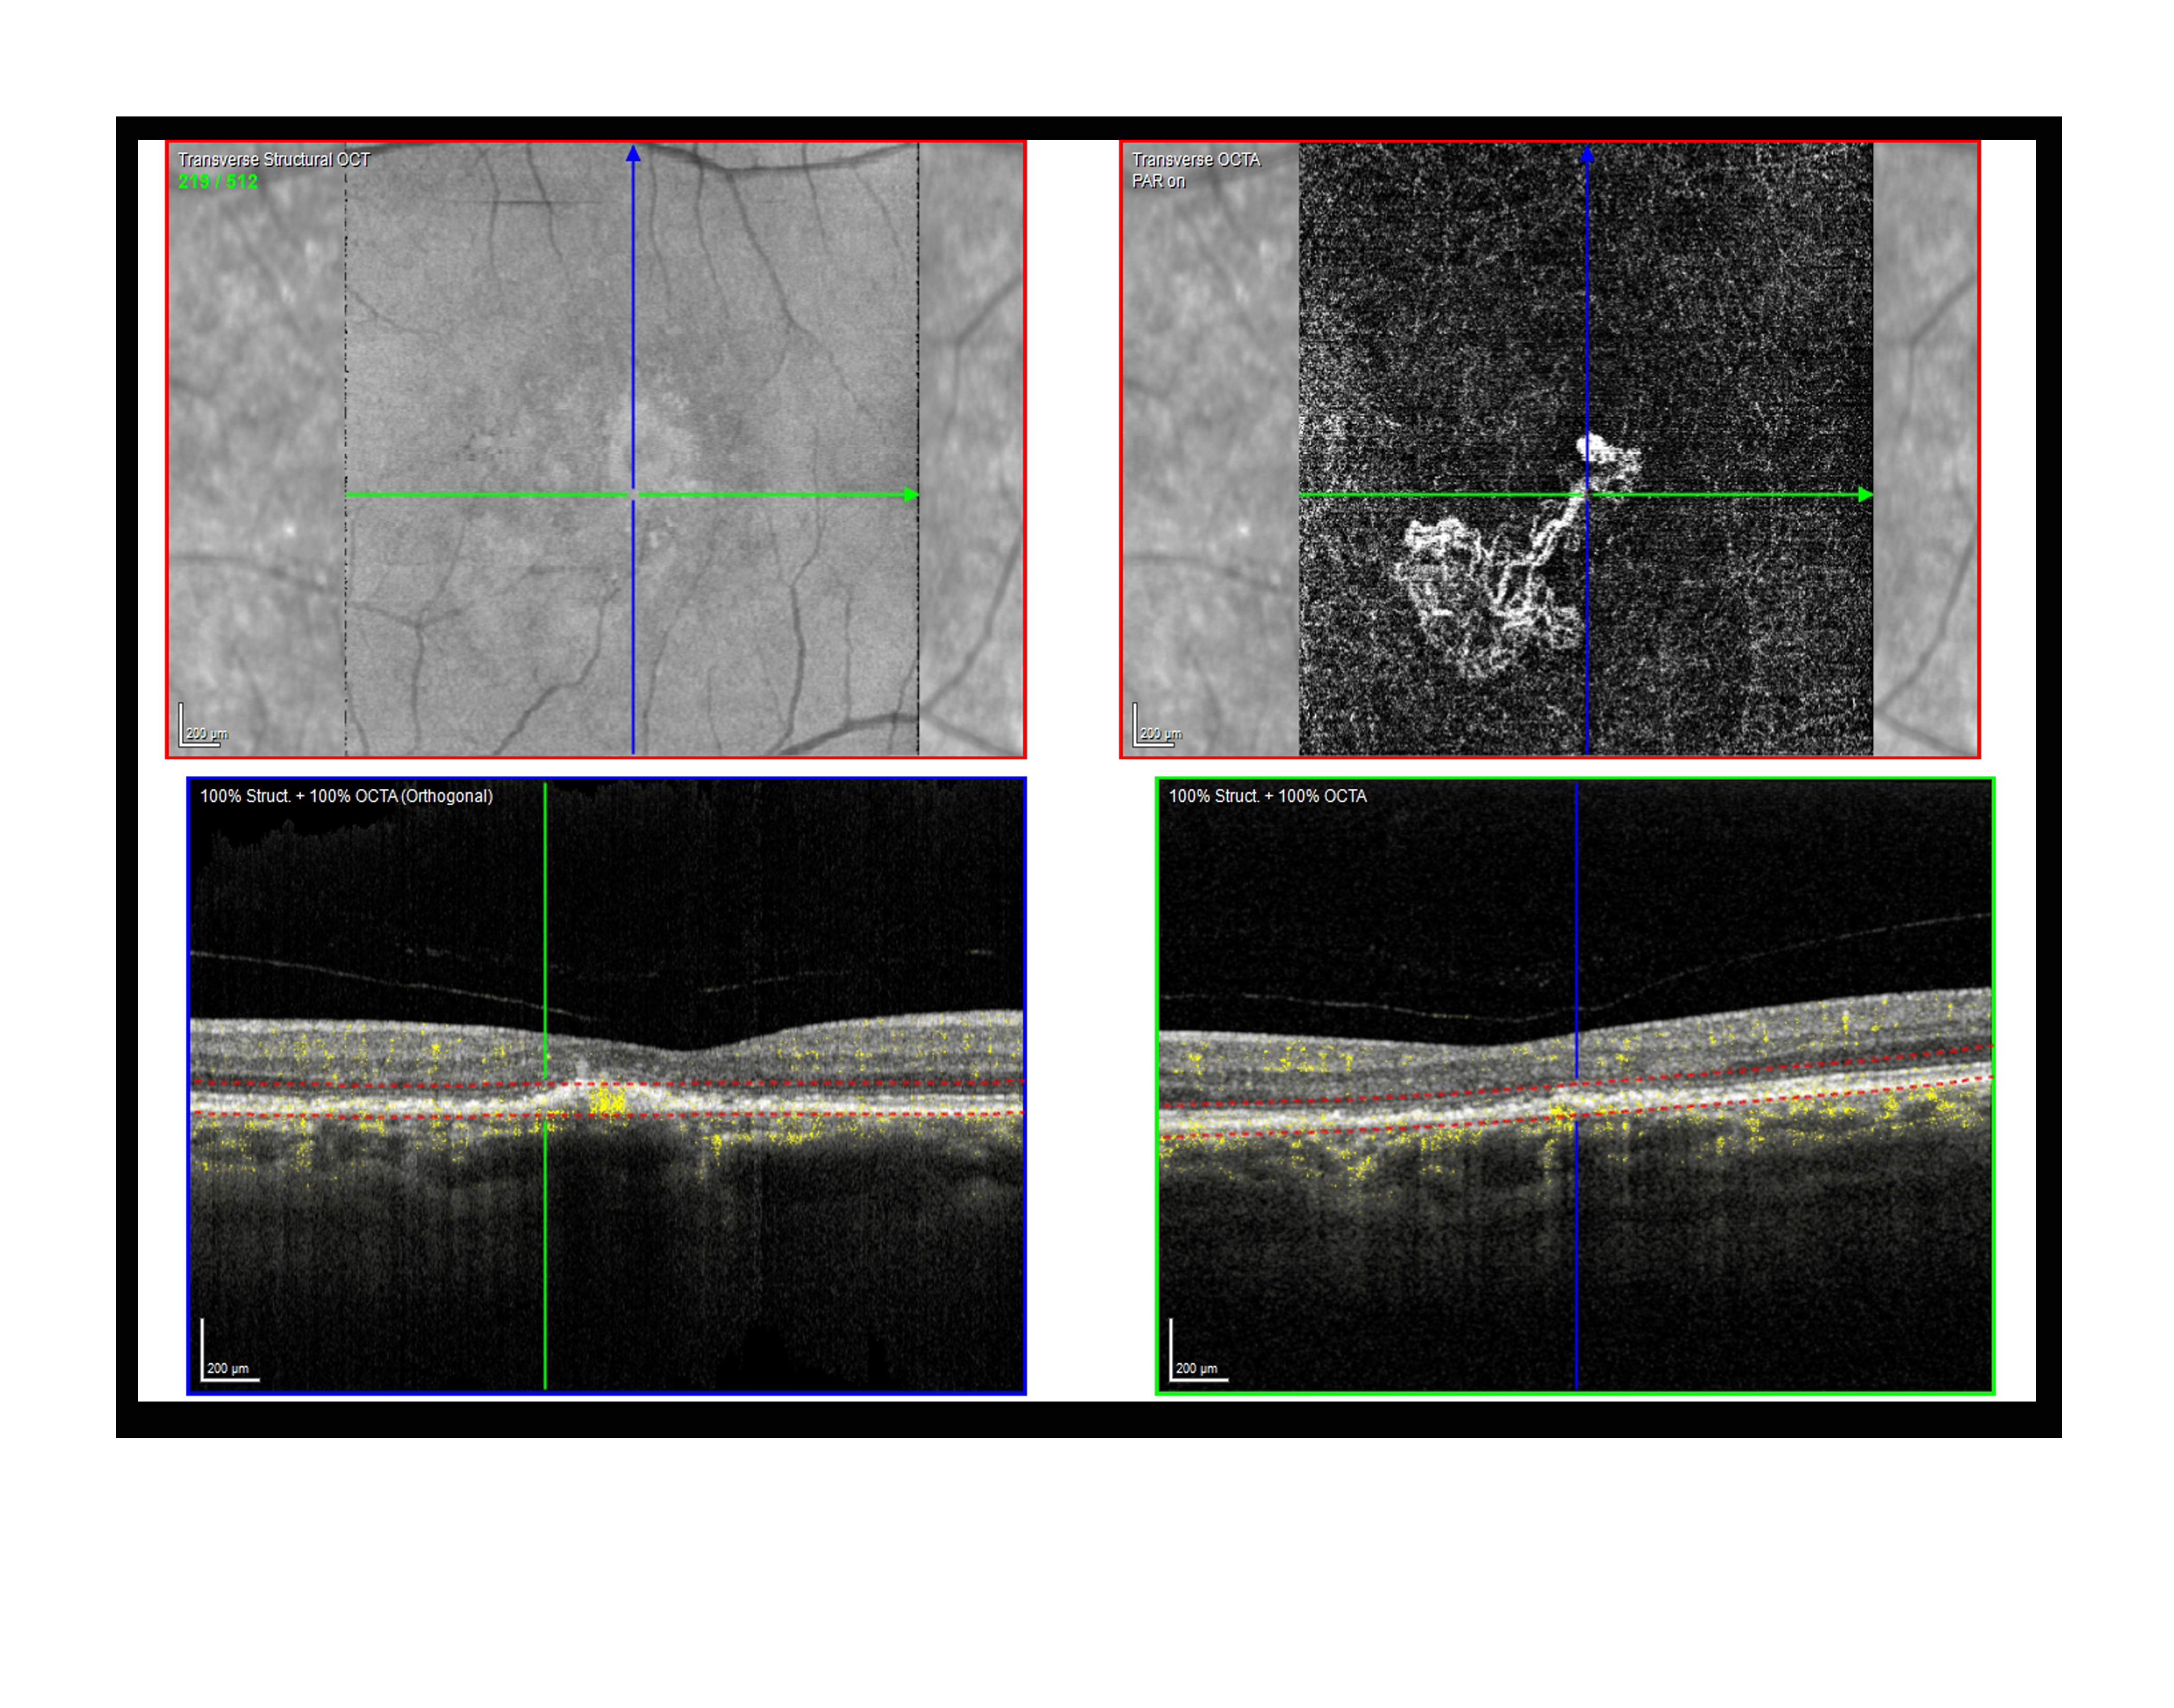

CNVM Presented by Paul Crown, CRA, OCT-C This photograph received Third Place in the category "Optical Coherence Tomography Angiography" and was displayed in the 2024 OPS Exhibit. Filed Under Retina OPS Photo